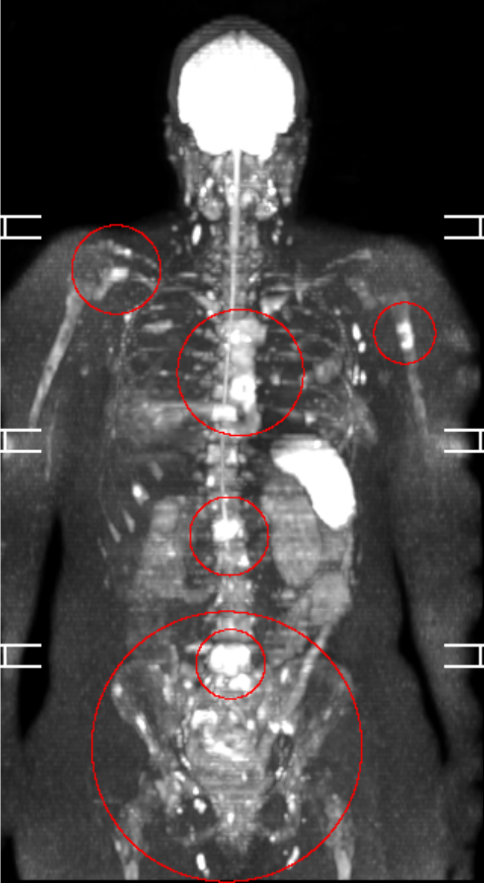

After being assured by Fred Hutchinson all was well following a lumpectomy in 2023, her naturopath was more vigilant and continued to monitor her closely. When her bloodwork began to show concerning findings, he ordered a full-body MRI scan in November 2025 (pictured above). The metastatic lesions had already spread through the pelvis, the entire spine, and the base of the long bones of her legs and arms. The image above devastated us. We called the boys up into our room and all wrapped ourselves around each other and Alicia. She has now lost 45 pounds, her body and her spirit are worn down to the bones. We must act now.

There is no cure or remission from this disease. For some with her diagnosis, the lesions quickly spread through the organs and all hope is lost. For the lucky ones with the correct supportive interventions, a longer, relatively high quality of life is achievable. Alicia has a concerning spot in her liver confirmed on her last PET scan. It was not biopsied. We are treating and hoping for the best at her upcoming follow-up scan.